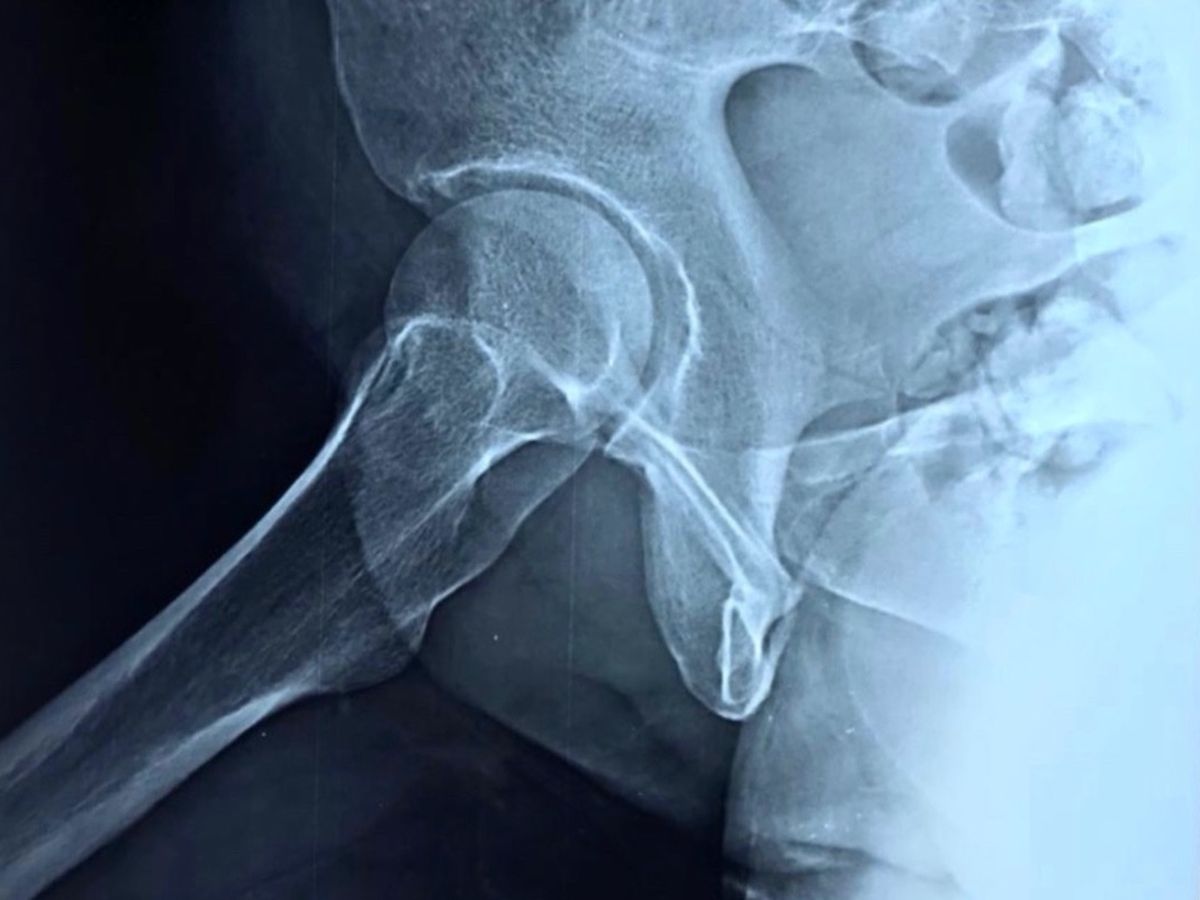

In February this year (2021), my mother was hit by a delivery van and they accidentally seriously fractured her hip bone. She couldn’t move for a month while she got rest & treatment. She had pre-existing issues with her uterus since December 2020.